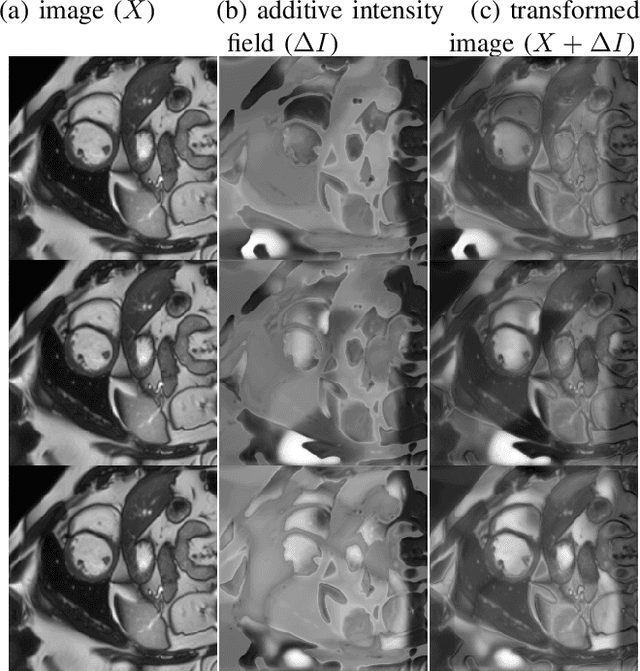

Abstract:Supervised learning-based segmentation methods typically require a large number of annotated training data to generalize well at test time. In medical applications, curating such datasets is not a favourable option because acquiring a large number of annotated samples from experts is time-consuming and expensive. Consequently, numerous methods have been proposed in the literature for learning with limited annotated examples. Unfortunately, the proposed approaches in the literature have not yet yielded significant gains over random data augmentation for image segmentation, where random augmentations themselves do not yield high accuracy. In this work, we propose a novel task-driven data augmentation method for learning with limited labeled data where the synthetic data generator, is optimized for the segmentation task. The generator of the proposed method models intensity and shape variations using two sets of transformations, as additive intensity transformations and deformation fields. Both transformations are optimized using labeled as well as unlabeled examples in a semi-supervised framework. Our experiments on three medical datasets, namely cardic, prostate and pancreas, show that the proposed approach significantly outperforms standard augmentation and semi-supervised approaches for image segmentation in the limited annotation setting. The code is made publicly available at https://github.com/krishnabits001/task$\_$driven$\_$data$\_$augmentation.

Abstract:Supervised deep learning methods for segmentation require large amounts of labelled training data, without which they are prone to overfitting, not generalizing well to unseen images. In practice, obtaining a large number of annotations from clinical experts is expensive and time-consuming. One way to address scarcity of annotated examples is data augmentation using random spatial and intensity transformations. Recently, it has been proposed to use generative models to synthesize realistic training examples, complementing the random augmentation. So far, these methods have yielded limited gains over the random augmentation. However, there is potential to improve the approach by (i) explicitly modeling deformation fields (non-affine spatial transformation) and intensity transformations and (ii) leveraging unlabelled data during the generative process. With this motivation, we propose a novel task-driven data augmentation method where to synthesize new training examples, a generative network explicitly models and applies deformation fields and additive intensity masks on existing labelled data, modeling shape and intensity variations, respectively. Crucially, the generative model is optimized to be conducive to the task, in this case segmentation, and constrained to match the distribution of images observed from labelled and unlabelled samples. Furthermore, explicit modeling of deformation fields allow synthesizing segmentation masks and images in exact correspondence by simply applying the generated transformation to an input image and the corresponding annotation. Our experiments on cardiac magnetic resonance images (MRI) showed that, for the task of segmentation in small training data scenarios, the proposed method substantially outperforms conventional augmentation techniques.